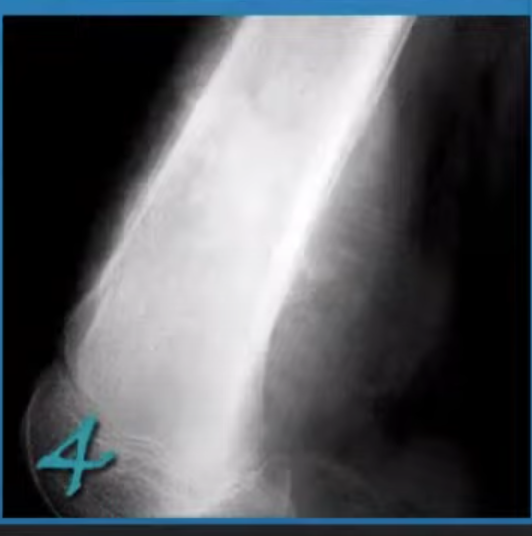

Plain radiograph

In the later stages features seen include:

flattening of the medial femoral condyle

subchondral radiolucent focus

complicating subchondral fracture with periosteal reaction